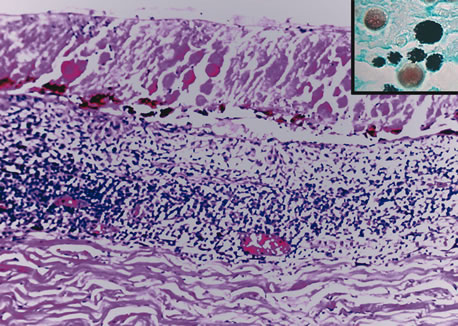

Inflammatory conditions may also lead to iris nodules. Patients suffering from fungal endophthalmitis may demonstrate an irregular yellow-white mass on the iris. Histologically, these appear as necrotizing granulomas containing mycotic agents (Fig. 2). In juvenile xanthogranuloma, a yellowish-gray iris lesion may be associated with spontaneous hyphema, and histopathologically the nodules demonstrate diffuse histiocytic infiltrate (Fig. 3). Multinucleated giant cells displaying peripheral foamy cytoplasm are also noted; these cells are known as Touton giant cells.29 The giant cells and the histiocytes contain lipid that can be demonstrated by oil red O stain.

Fig. 3. Juvenile xanthogranuloma. The iris is infiltrated by histiocytes, which form nodular aggregates on the anterior surface of the iris. (Hemotoxylin-eosin ×25.) Inset (×200) shows oil red O-positive histiocytes.